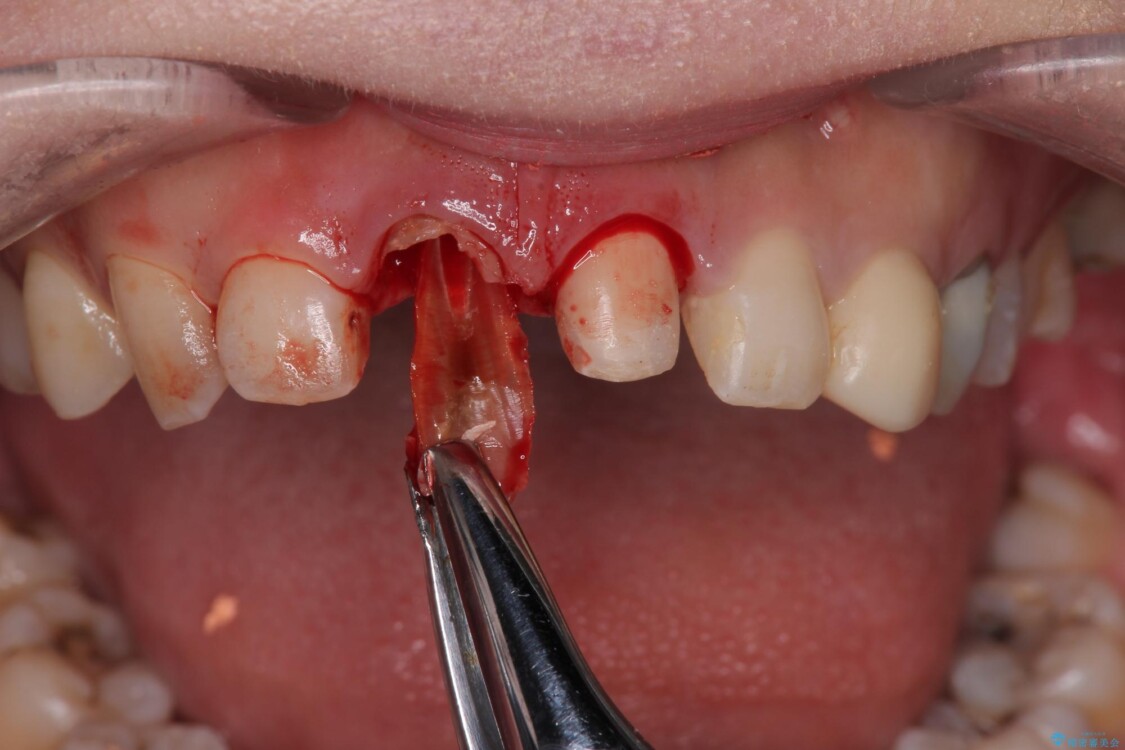

▶右上中切歯

抜歯後、即時インプラント埋入

審美性を考慮し、仮歯を即日装着

治療期間を最小限に抑えつつ、自然な前歯のラインと歯ぐきの形を維持

治療途中

• 「抜歯してブリッジ」と言われた20代女性が選んだ治療とは|たった4か月で自然な笑顔に抜歯即時インプラント+審美補綴の症例 治療途中画像